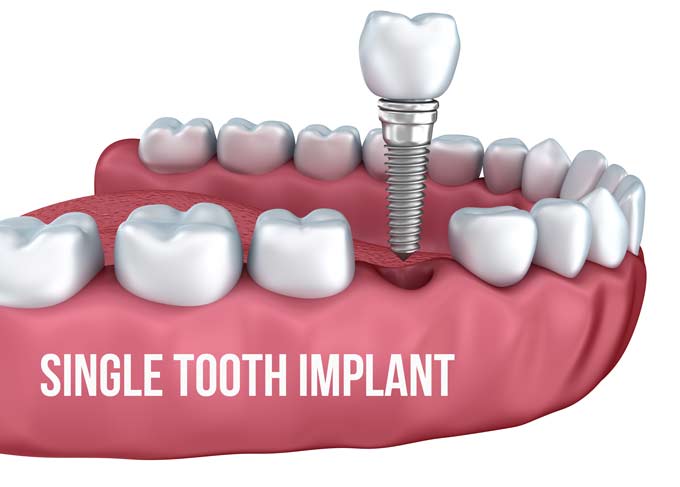

Is there a cheaper alternative to dental implants?

What are dental bridges? A dental bridge is a cheaper alternative to dental implants, but it is not suitable for all situations. If you are not quite ready for dentures, you can consider the following: Bridge connected with glue: This type has wings on each side of the false tooth.

What is the downside of dental implants?

The most common disadvantage of dental implant placement is that it is an expensive procedure and the insurance provider does not always have to cover it. Additional potential disadvantages of dental implants include: pain, swelling and bleeding due to surgery. Complications of anesthesia such as nausea, vomiting and drowsiness.

Why dental implants are bad?

When oral hygiene fails, both the teeth (or dental implant) and surrounding tissue (gums, periodontium, and alveolar bone) undergo high concentrations of microbial products, which can cause decay, gingivitis, periodontitis, or peri-implantitis.